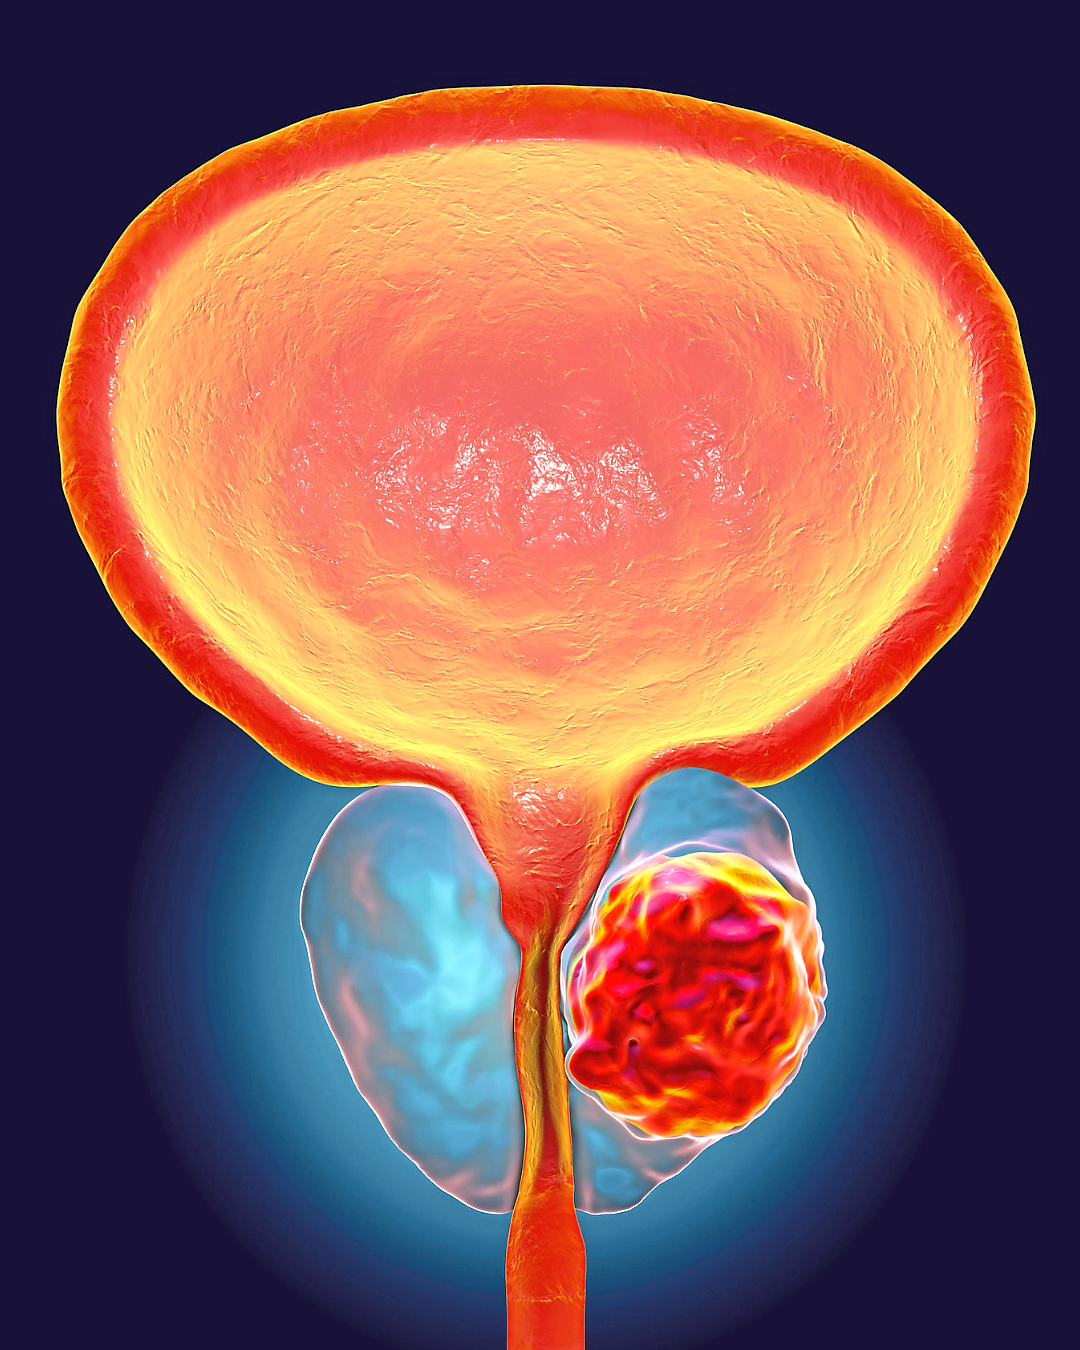

The frequency of prostate cancer is rising rapidly and is expected to double within the next 10 to 15 years.

In 2020, there were approximately 1.4 million new cases worldwide, with 375,000 deaths annually.

By 2040, the World Health Organization (WHO) predicts there will be nearly 2.9 million cases and 750,000 deaths each year.

Every clinically significant prostate cancer has the potential to cause harm, and every cancer begins as a small lesion before growing into a life-threatening disease.

One of the most important insights in modern urology is that not all prostate cancers are inherently life-threatening.

Many are slow-growing and may never cause harm during a man’s lifetime.